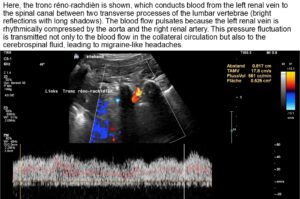

A collateral circulation branches off from the left renal vein to the spinal canal—a so-called tronc réno-rachidièn—which feeds 148 ml/min into the epidural plexus in a horizontal body position. When standing, the perfusion of the vessel increases to 531 ml/min.

This contributes to an increase in pressure in the spinal canal and subsequently intracranially, which would explain headaches and, in some cases, neurological deficits in the cranial nerves (visual disturbances, speech disorders, bulbar motility disorder). The drastic increase in spinal and thus cerebral congestion when standing after eating. This corresponds exactly with the patient’s description of unbearable headaches after every meal.

- Collateralization of renal vein blood, including into the spinal canal via a tronc réno-rachidièn, resulting in increased postprandial spinal and cerebral congestion